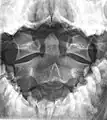

![]() Second cervical vertebra, or epistropheus, from above | |

In anatomy, the axis (from Latin axis, "axle") is the second cervical vertebra (C2) of the spine, immediately inferior to the atlas, upon which the head rests.

The axis' defining feature is its strong odontoid process (bony protrusion) known as the dens, which rises dorsally from the rest of the bone.